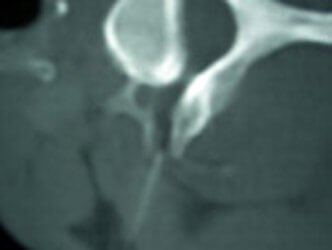

Bilder zu Injektionstherapie und CT-Injektionen

Bildwandlergesteuerte mikrotechnische Injektionstherapie und CT-Injektionen.

Je nachdem, ob Arthrose die Ursache für die Rückenbeschwerden ist oder ein Bandscheibenvorfall vorliegt, kann man mit einem Kontrastmittel zielgerichtet entsprechende Medikamente an den Ort der Ursache spritzen. Hierbei verwenden wir Mikro-Kanülen. Dieser Injektionsvorgang ist deutlich weniger schmerzhaft als eine vergleichbare Spritze in den Muskel.

Hier besteht ebenfalls wie bei dem uns zur Verfügung stehenden Computertomographen die Möglichkeit, z. B. auch entsprechende Knorpelsubstanzmittel direkt an den Ort des Verschleißes zu injizieren (CT-Injektionen). Darüber hinaus können abschwellende Medikamente oder gentechnologische Produkte an den Ort von Bandscheibenvorfällen appliziert werden, um so das bestehende ödem und daraus folgend den Nerv zu entlasten. Damit können Operationen häufig unnötig werden.